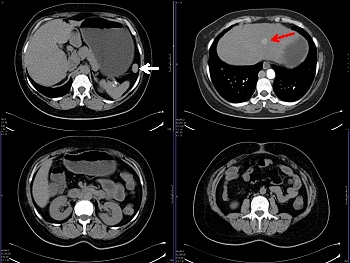

Un estudio de tomografía computada (TC) abdominal con contraste realizado más tarde demostró la presencia de un bazo accesorio correspondiendo a la zona de captación focal del 68Ga-dotatate (fig. 3, flecha blanca). Ambas glándulas suprarrenales eran normales en tamaño y morfología, sin formaciones nodulares. Se identificó, además, una lesión hipervascularizada en el lóbulo izquierdo del hígado, localizada centralmente en el segmento 2, de aproximadamente 1cm de diámetro (flecha roja), que no exhibía expresión de receptores de la somatostatina en el PET; fue interpretada como posible implante secundario o hiperplasia nodular focal.